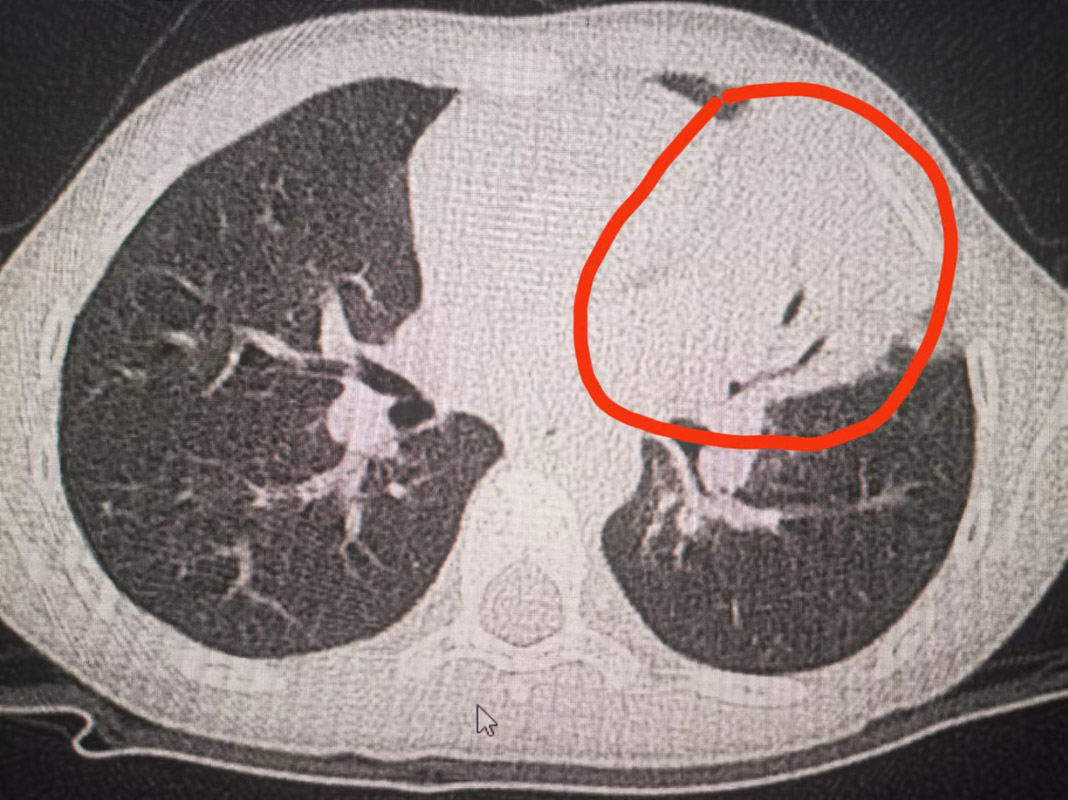

6歲鵬鵬的病情與小萱相似。鵬鵬的媽媽稱,孩子以前發(fā)熱、咳嗽,在家吃一兩次退燒藥就好了。但這次,鵬鵬發(fā)熱4天,吃藥也難以退至正常,且咳嗽劇烈。到醫(yī)院就診后,鵬鵬的檢查報(bào)告顯示,胸部CT也出現(xiàn)左下肺大片感染灶,肺炎支原體IgM抗體也呈陽(yáng)性。